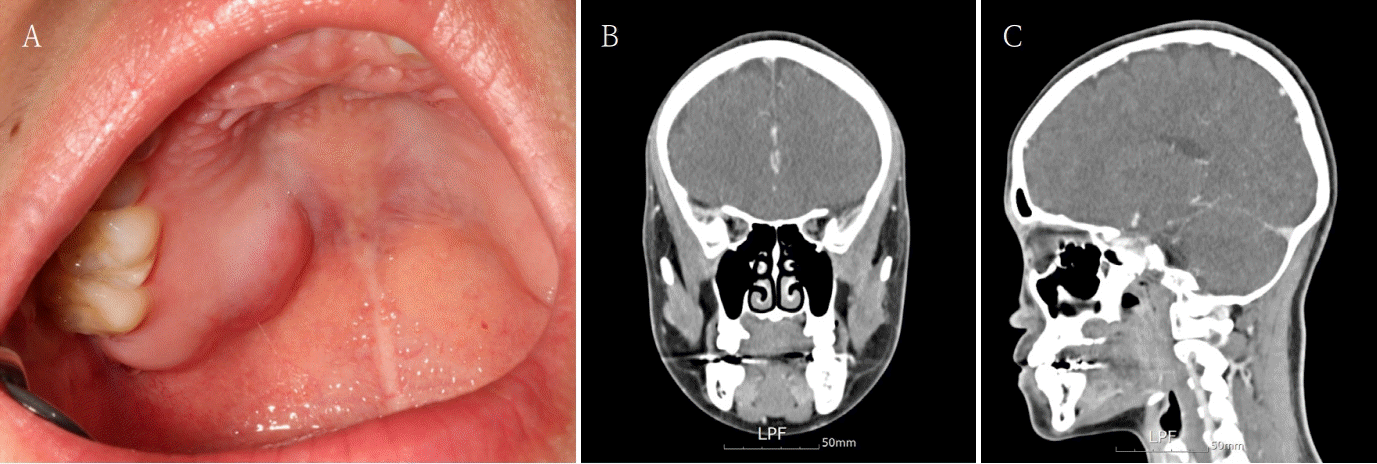

A 26-year-old female patient was referred to our clinic for definitive diagnosis and treatment due to bulging lesion on the right posterior palatal region. The patient reported being aware of the lesion for approximately one month. Notable swelling was observed in the right posterior hard palate. Upon palpation, a firm swelling exhibiting slight elasticity was noted, without any evidence of fluctuation. The lesion did not extend beyond the palatal midline and measured approximately 2.5 cm x 2 cm x 2 cm. There was no color change on the overlying mucosa and the surface of the lesion was smooth without ulcers (Fig. 1A). It revealed no pain, and aspiration yielded no content. Adjacent teeth showed no clinical features such as pain or discomfort, and the palate involving the lesion exhibited no sensory abnormalities.A facial CT was performed, which revealed a 16 mm x 12 mm x 12 mm radiolucent cystic lesion with central faint high-density content (Figs. 1B and C). Incision biopsy was also done. Histopathological results confirmed the diagnosis of pleomorphic adenoma. Considering the possibility of recurrence, it was decided to exercise both the lesion and the overlying mucosa under general anesthesia. For the surgical defect that may arise postoperatively, a buccal fat pad free graft was designated as the reconstructive method. Under general anesthesia, a mass excision in the right palate with a buccal fat pad free graft was performed. The lesion with overlying mucosa was excised using an electrocautery device. The size of the excised lesion was approximately 2.5 cm x 2 cm x 2 cm. The border of the lesion was clear without adhesion. bony erosion of the palatal region was observed at the lesion site, with no evidence of maxillary sinus perforation. The posterior area of the right maxillary second molar was incised, and the dissection was performed to expose the buccal fat pad. A portion of the exposed fat pad was harvested and grafted into an excised defect as a free graft. The grafted buccal fat pad was sutured to the surrounding mucosa (Fig. 2). A prefabricated palatal shell was placed to protect the surgical field. Histopathological result of the excised lesion confirmed pleomorphic adenoma, with tumor-free resection margins. During the hospitalization period, the grafted buccal fat pad remained stable without evidence of complications.Three weeks postoperatively, the grafted buccal fat pad was observed to have remained viable without necrosis or infection. One month postoperatively, epithelialization of the grafted fat pad was noted, and the sutures were removed. At the two-month follow-up, the epithelialization of the grafted site had progressed without any complications. Finally at the eight-month follow-up, there was no recurrence. More follow up will be needed (Fig. 3).

Fig. 1.

A. A round, protruding lesion is observed in the posterior region of the right hard palate, with no associated symptoms such as pain. B and C. Facial CT images show no significant changes in size or bone destruction compared to the previous examination.